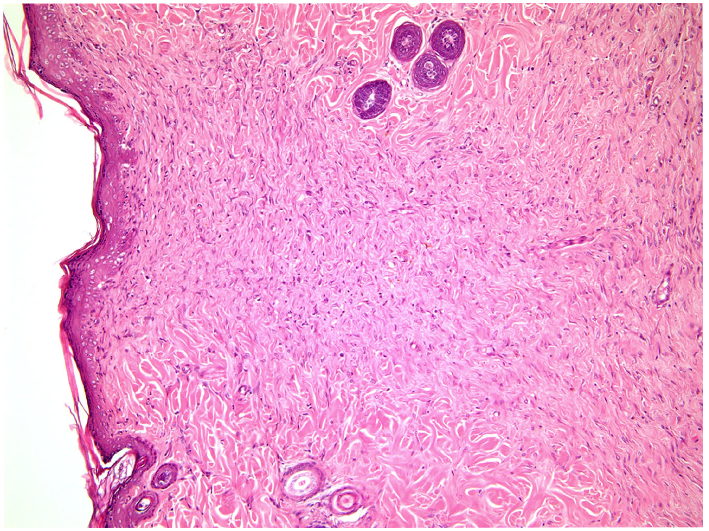

—fibrin clot,

—granulation tissue,

—adipose tissue.